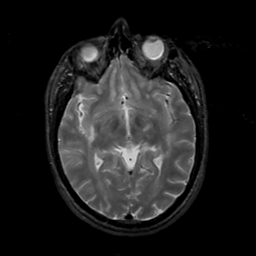

MR Study #6, March 17, 1991 -- Slice #23

[Home][Help][Clinical][Tour 1][Tour 2] Slice 23